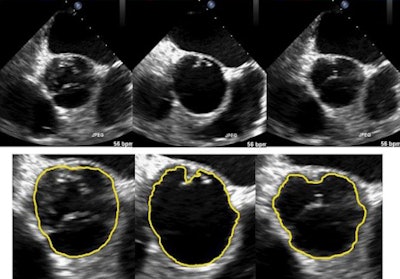

The algorithm uses a mathematically based framework that can efficiently track moving boundaries on ultrasound videos, making it suitable for real-time clinical applications, according to the researchers from Shanghai Jiao Tong University, Peking University, and the National University of Singapore. In testing on two ultrasound video datasets, the technique's segmentation quality and computational time compared favorably with other ultrasound segmentation approaches.

The group developed the software algorithm to address issues commonly encountered with segmentation of ultrasound studies. While segmentation techniques can help identify boundaries and regions of interest that facilitate image interpretation, efficient segmentation of ultrasound videos is often complicated by low contrast, shadow effects, and complex "noise" statistics (i.e., unexplained variations). Real-time applications such as ultrasound-guided surgery also require efficient algorithms, according to the researchers.

In contrast with other ultrasound segmentation techniques, the group's model relies on variational methods, which are commonly used for motion and edge detection due to their modeling flexibility, the researchers noted. In addition, the technique incorporates wavelet frames, which are well-suited for efficient segmentation of low-quality footage such as ultrasound videos.